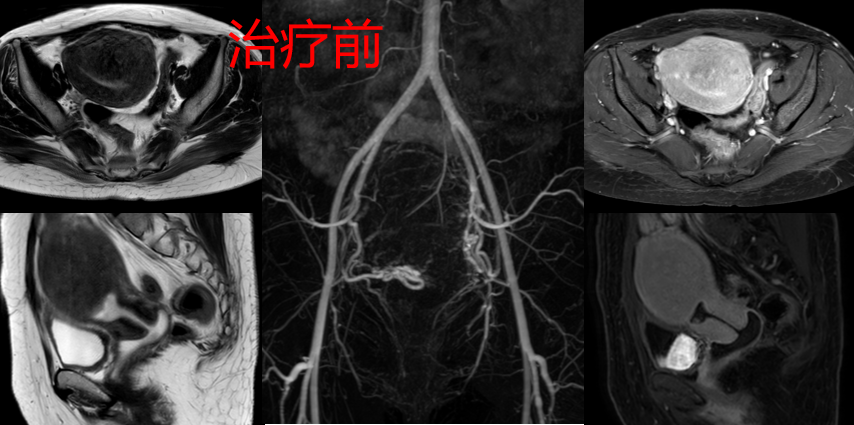

39岁的曾女士,一天上洗手间的次数竟是普通人的三倍之多,来例假时痛经不光肚子疼,连腰骶部都坠胀得难受,经常在经期疼得直不起腰,严重影响了她的工作生活。而且月经量也比以前明显增多,体力降低,易疲劳。以往家住5楼的她一口气可以爬上去,而如今,5层楼她中途需要歇个两三回。同时,曾女士还发现自己的小肚子日益增大,小便也越来越憋不住了,出门在外一有尿感就得赶快找厕所。这样的尿频、尿急情况持续了一年之久。刚开始她只觉得自己是因为上了年纪,身体素质下降而导致的痛经和尿频,直到后来月经出现淋漓不净,这才考虑到是妇科疾病,到当地医院就诊,诊断是子宫腺肌病,医生建议,如果曾女士不打算生娃就把子宫切除了。后来曾女士开始在网上搜索各种资料,她看到一篇公众号得知子宫腺肌症导致的痛经、尿频、尿急可以通过”介入微创保宫治疗“好转。曾女士遂在“广东省第二人民医院公众号”上挂号预约韦文姜副主任医师的号后来到广东省第二人民医院介入血管科门诊就诊,门诊磁共振MRA检查显示:“子宫明显增大,大小约为108mm*92mm*63mm”(如下图),“子宫腺肌症”也就是导致曾女士经期痛不欲生、尿频、夜尿增多的元凶。